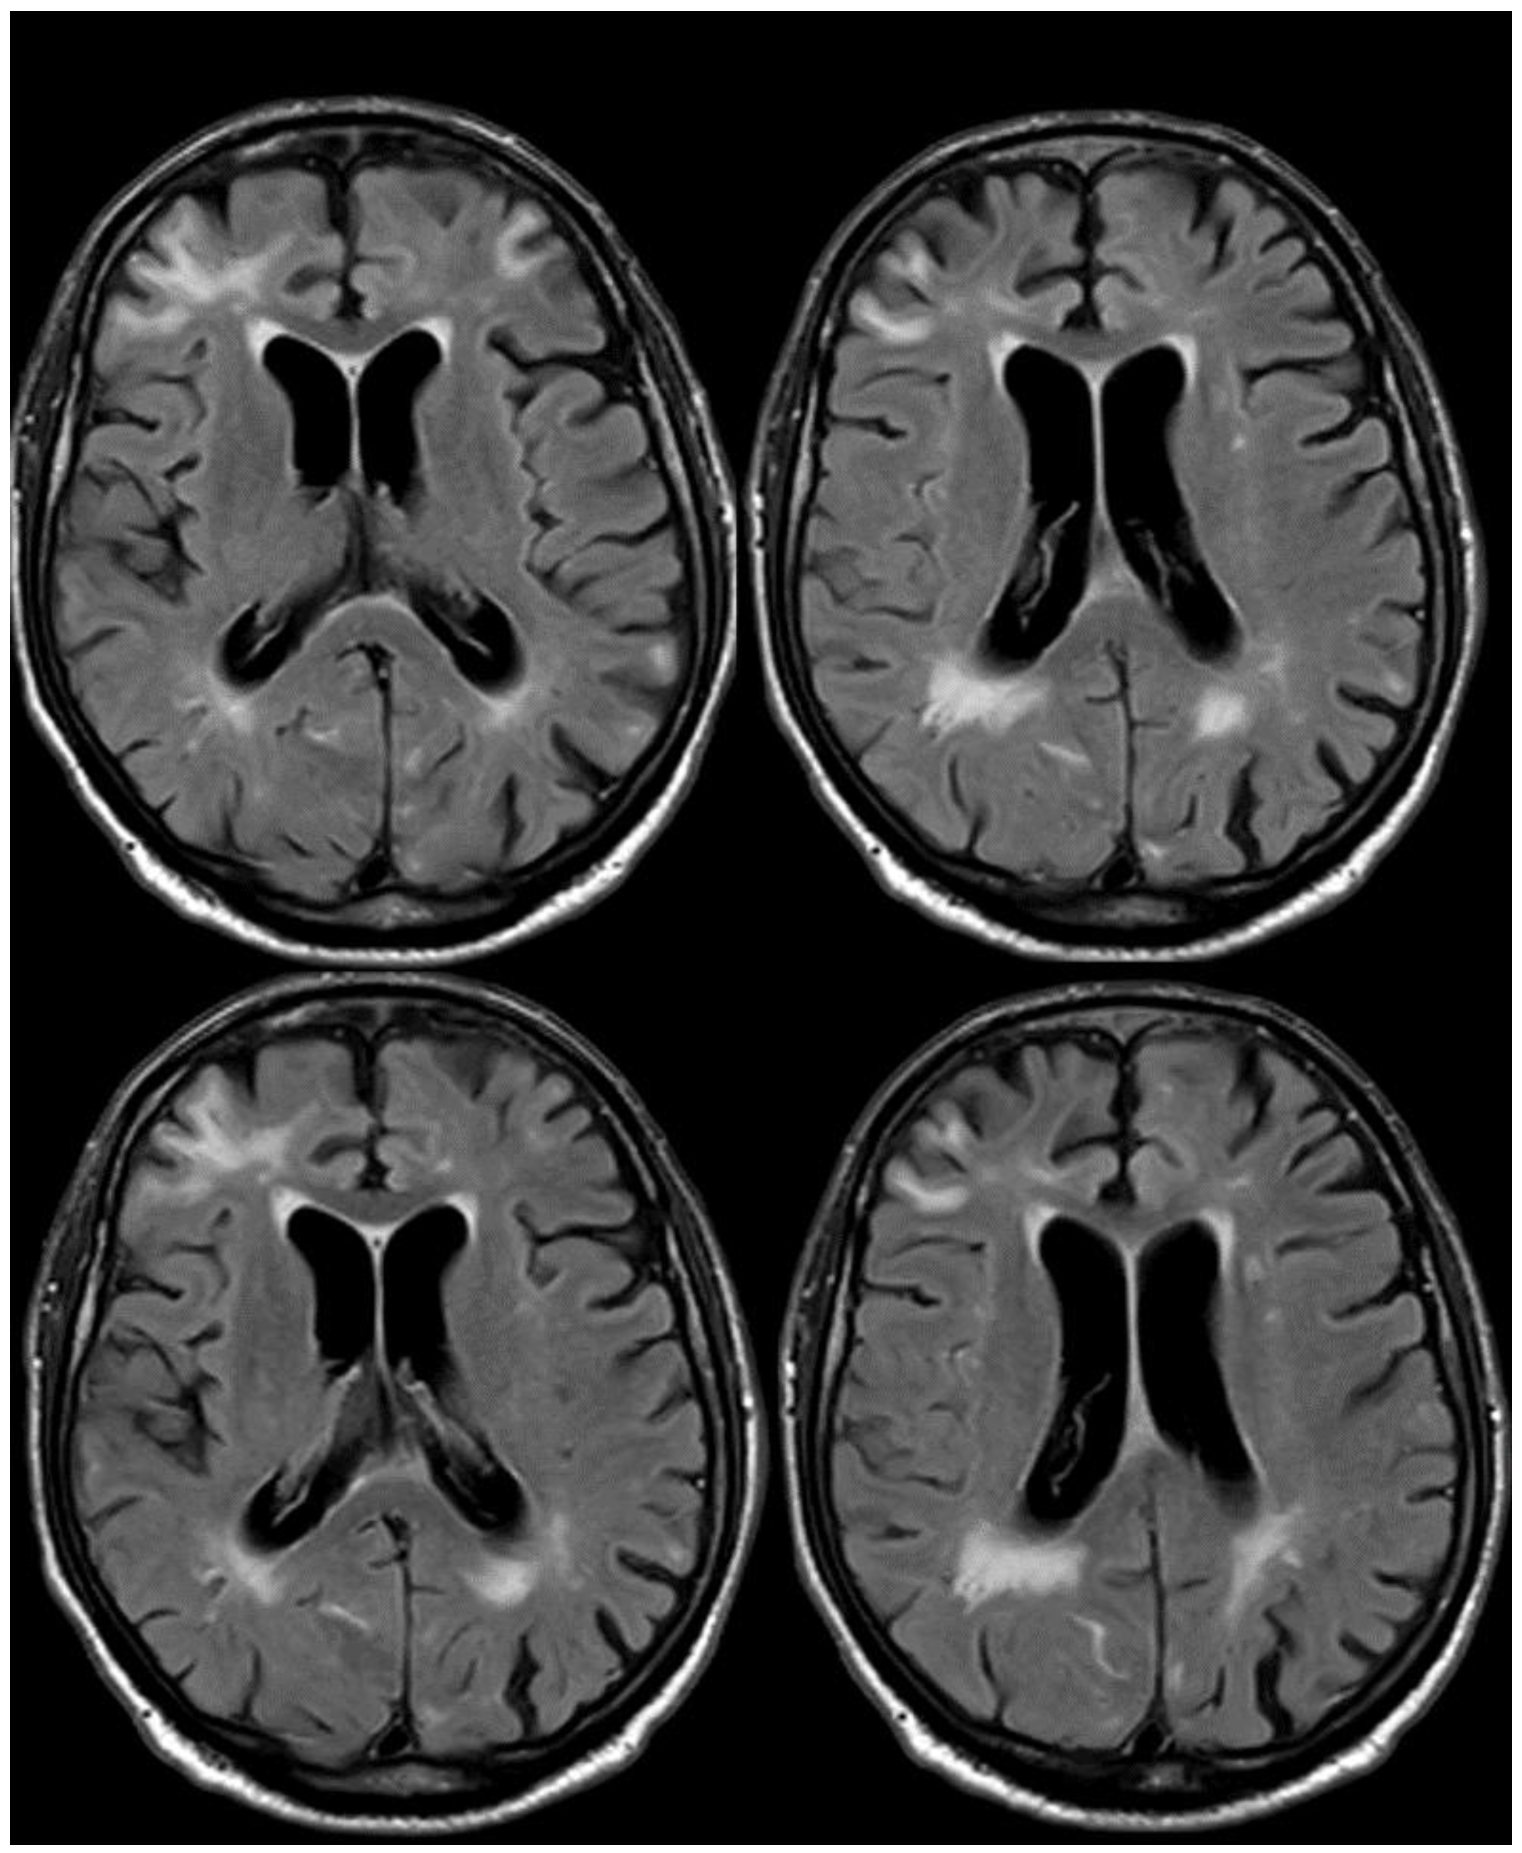

4. December 2015: Ischemic Stroke